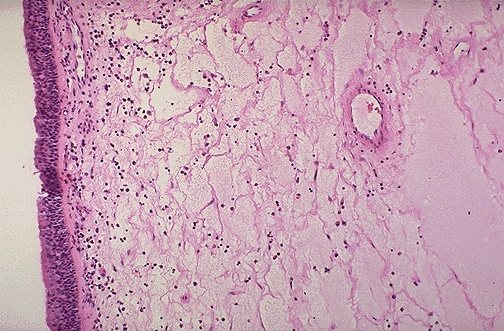

As seen here at low power, there is overlying respiratory mucosa at the left, with an edematous stroma.